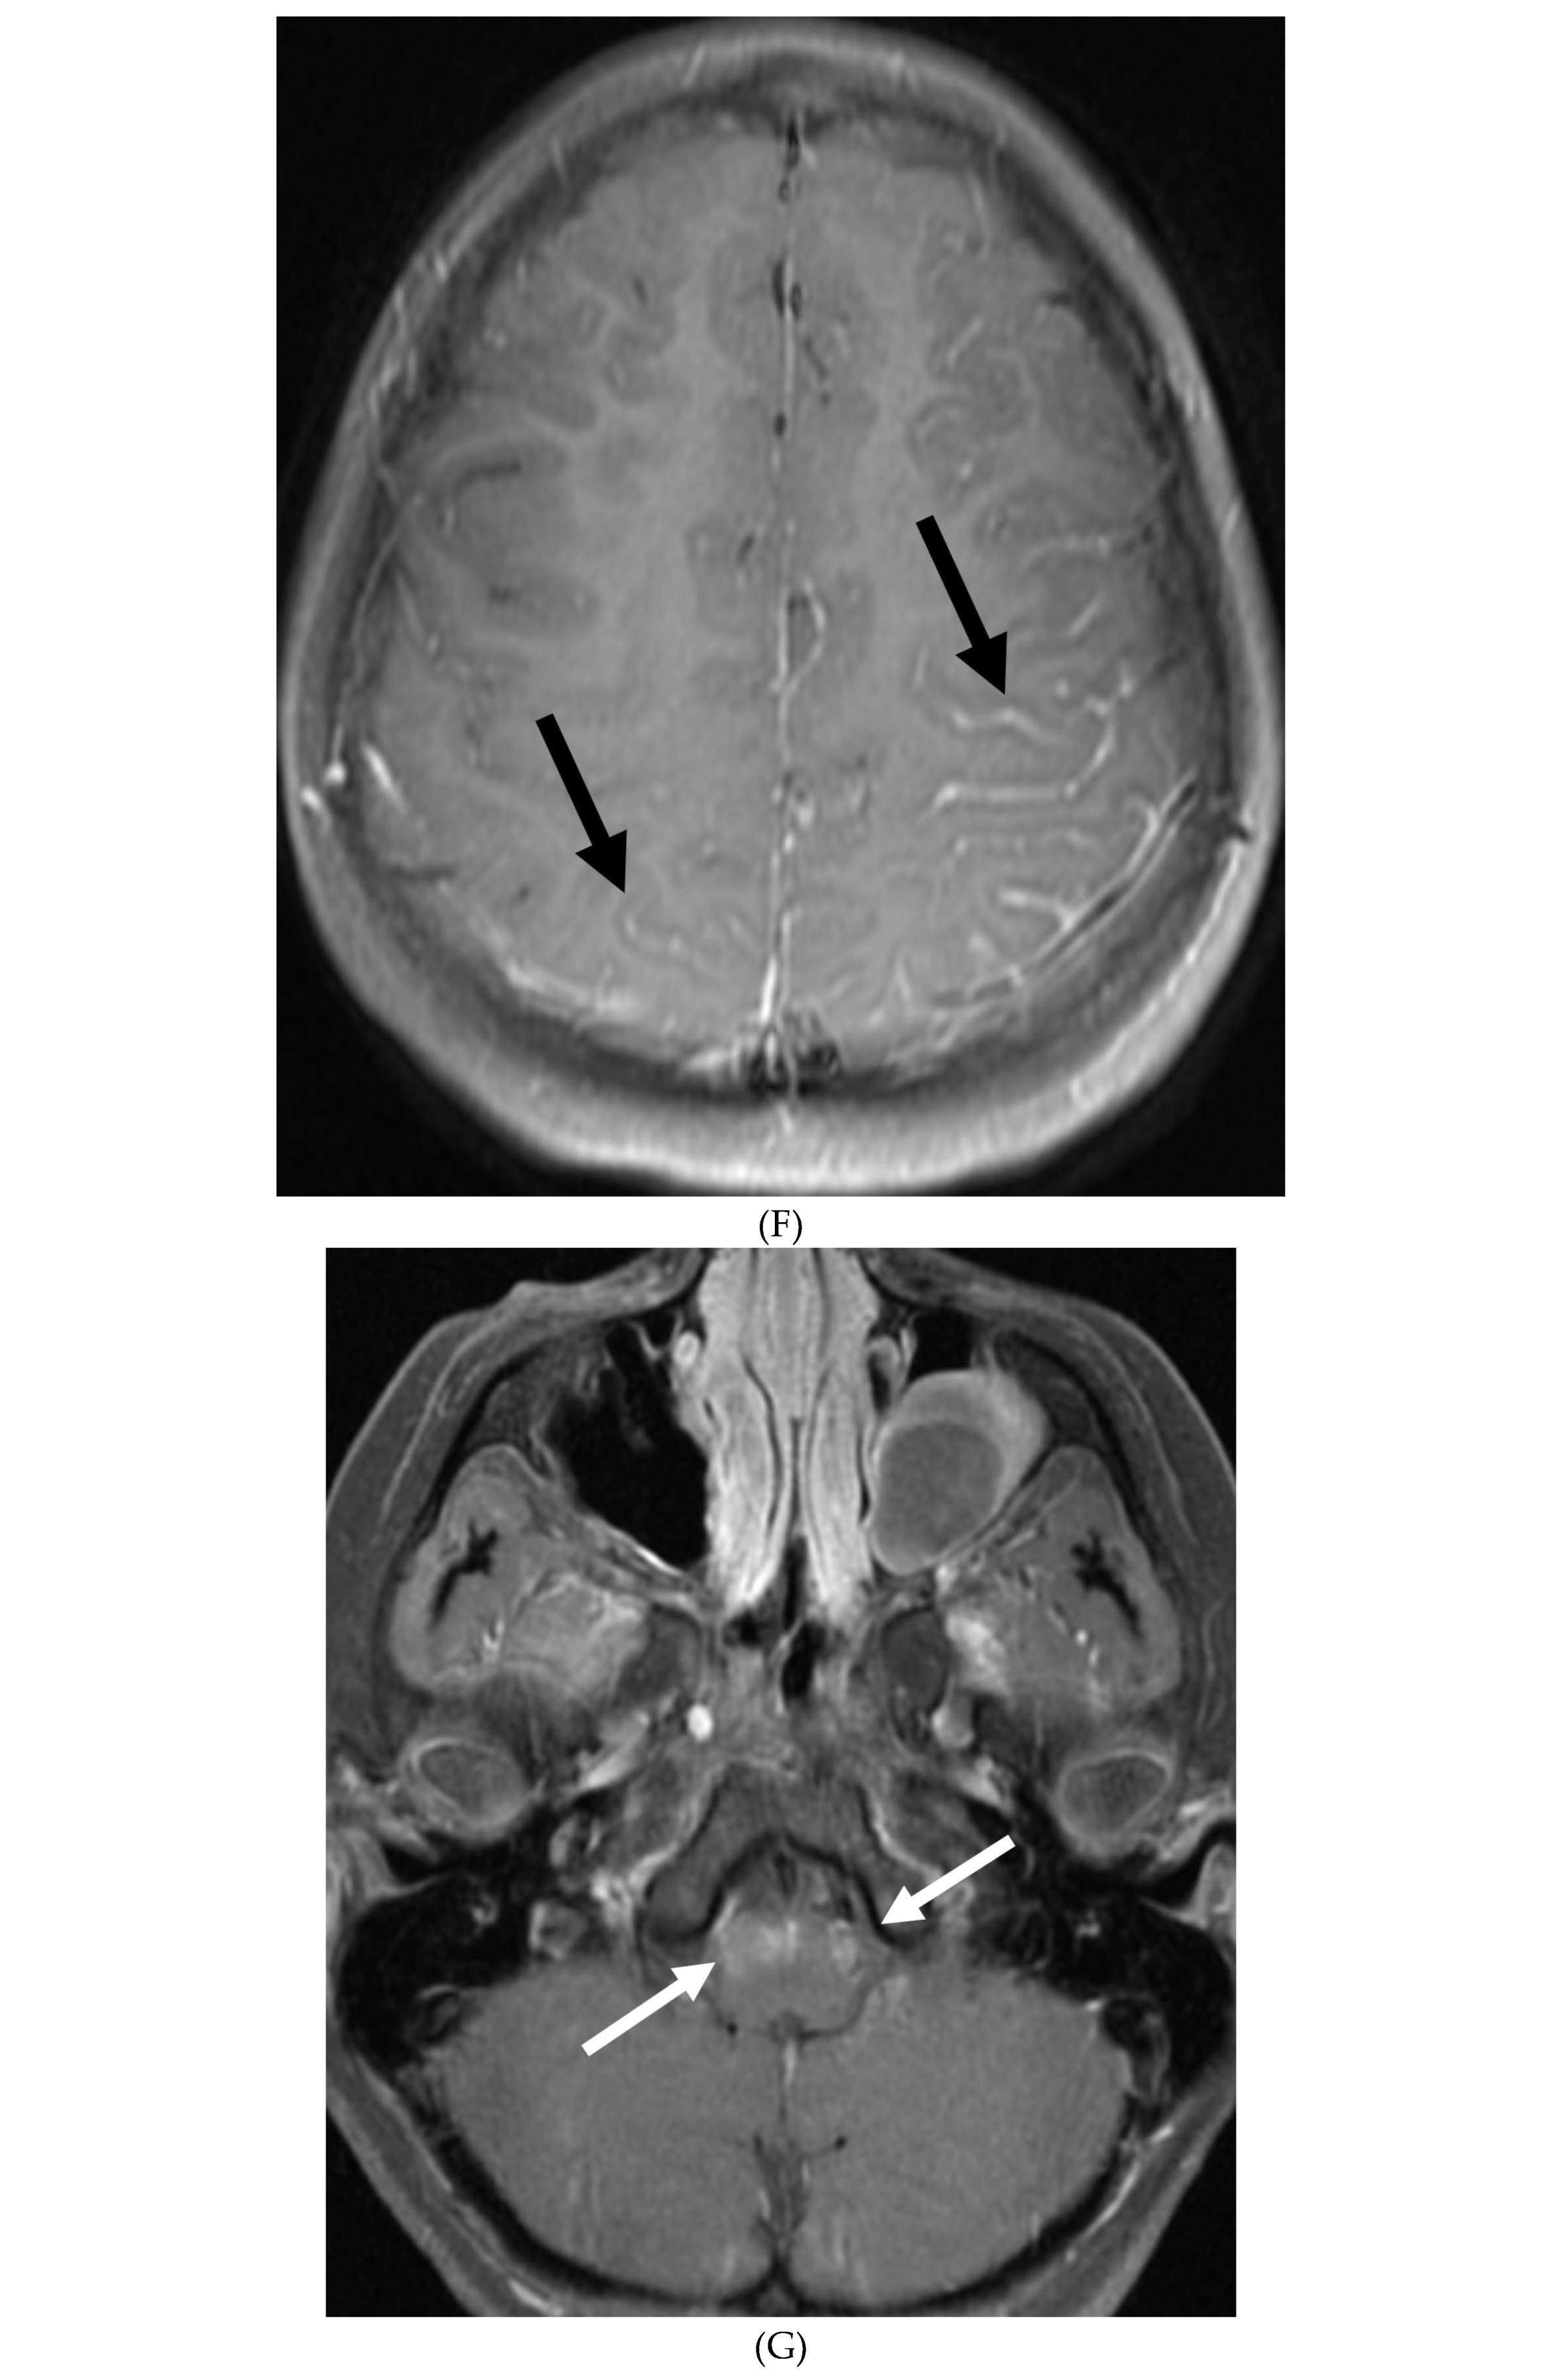

INTRACRANIAL HYPOTENSION (IH)